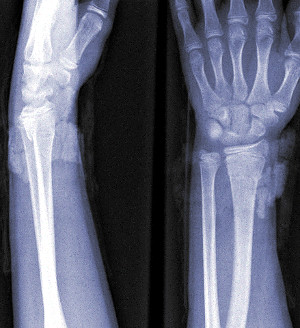

对象全身遍布多处磨损与皮肤撕脱伤。沿前臂有多处撕裂伤,左桡骨有一处骨折。双眼被剜出。

实验室数据:基因分析确认人类DNA。额外的X染色体(XXY)表明存在克兰费尔特综合征,但有非典型表现(对象的骨骼系统表现为女性而非男性)。与SCP-2679-B-075极为匹配。

对象全身遍布多处磨损与皮肤撕脱伤。多处骨折与骨碎,特别是沿上颌骨与鼻骨。3颗牙齿(2颗上颚,1颗下颚)破碎。